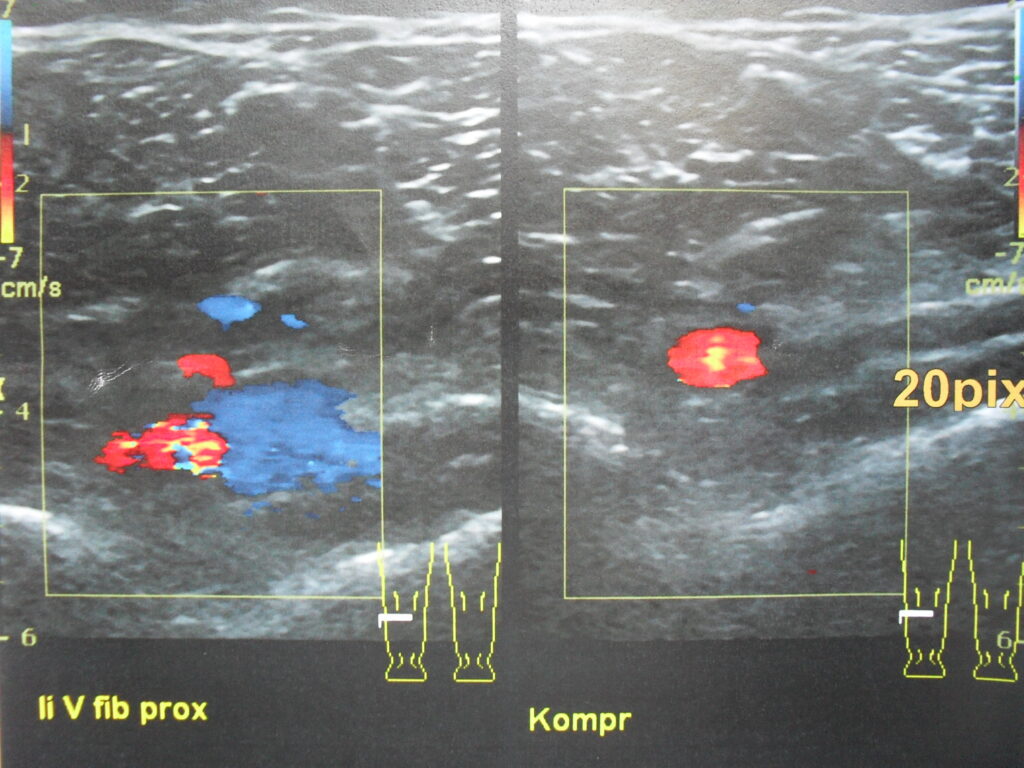

I underwent a chest x-ray (spiral CT scan), followed by an ultrasound. These revealed clots in both lungs and my left calf.